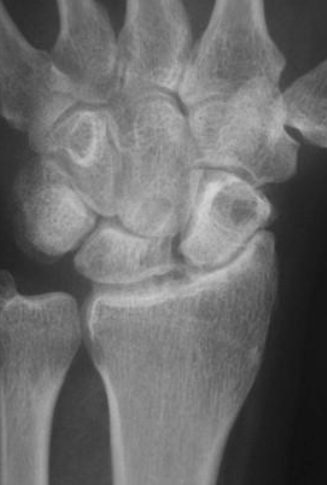

What is seen in SLAC stage 1 on xray

PA radiograph